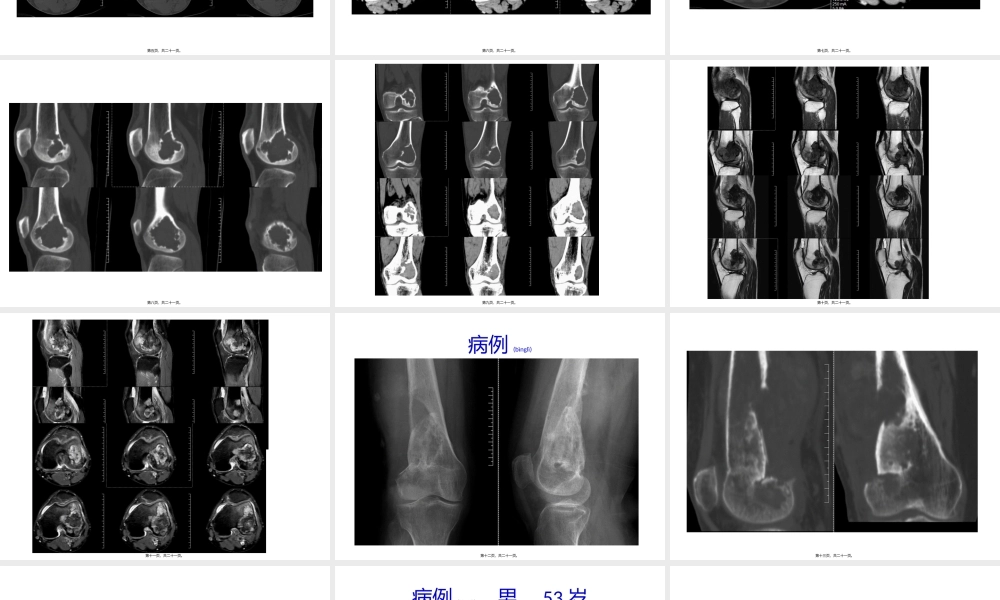

病例(bìnglì)一第一页,共二十一页。放射科第二页,共二十一页。临床(línchuánɡ)病史男,61岁,5天前无明显原因出现左膝部疼“痛、活动受限,到医院经拍片检查提示左股骨远端”占位,建议到上级医院治疗;现为进一步治疗,今“”转入我院求治。门诊经检查后以左股骨远端占位为诊断收入我科。发病以来,神志清楚,精神尚可,无恶寒发热,饮食、大小便正常,睡眠可,体重无明显变化。无肝炎、结核等传染病史,无其它外伤、手术史,无输血、中毒史,无明确(míngquè)药物过敏史,随社会预防接种。第三页,共二十一页。平片第四页,共二十一页。第五页,共二十一页。第六页,共二十一页。第七页,共二十一页。第八页,共二十一页。第九页,共二十一页。第十页,共二十一页。第十一页,共二十一页。病例(bìnglì)第十二页,共二十一页。第十三页,共二十一页。第十四页,共二十一页。病例(bìnglì),男,53岁第十五页,共二十一页。第十六页,共二十一页。第十七页,共二十一页。第十八页,共二十一页。病例(bìnglì),女,47第十九页,共二十一页。第二十页,共二十一页。内容(nèiróng)总结病例一。男,61岁,5天前无明显原因出现左膝部疼痛、活动受限,到医院“”经拍片检查提示左股骨远端占位,建议到上级医院治疗。无肝炎、结核等传染病史,无其它(qítā)外伤、手术史,无输血、中毒史,无明确药物过敏史,随社会预防接种。平片。病例。病例,男,53岁。病例,女,47第二十一页,共二十一页。